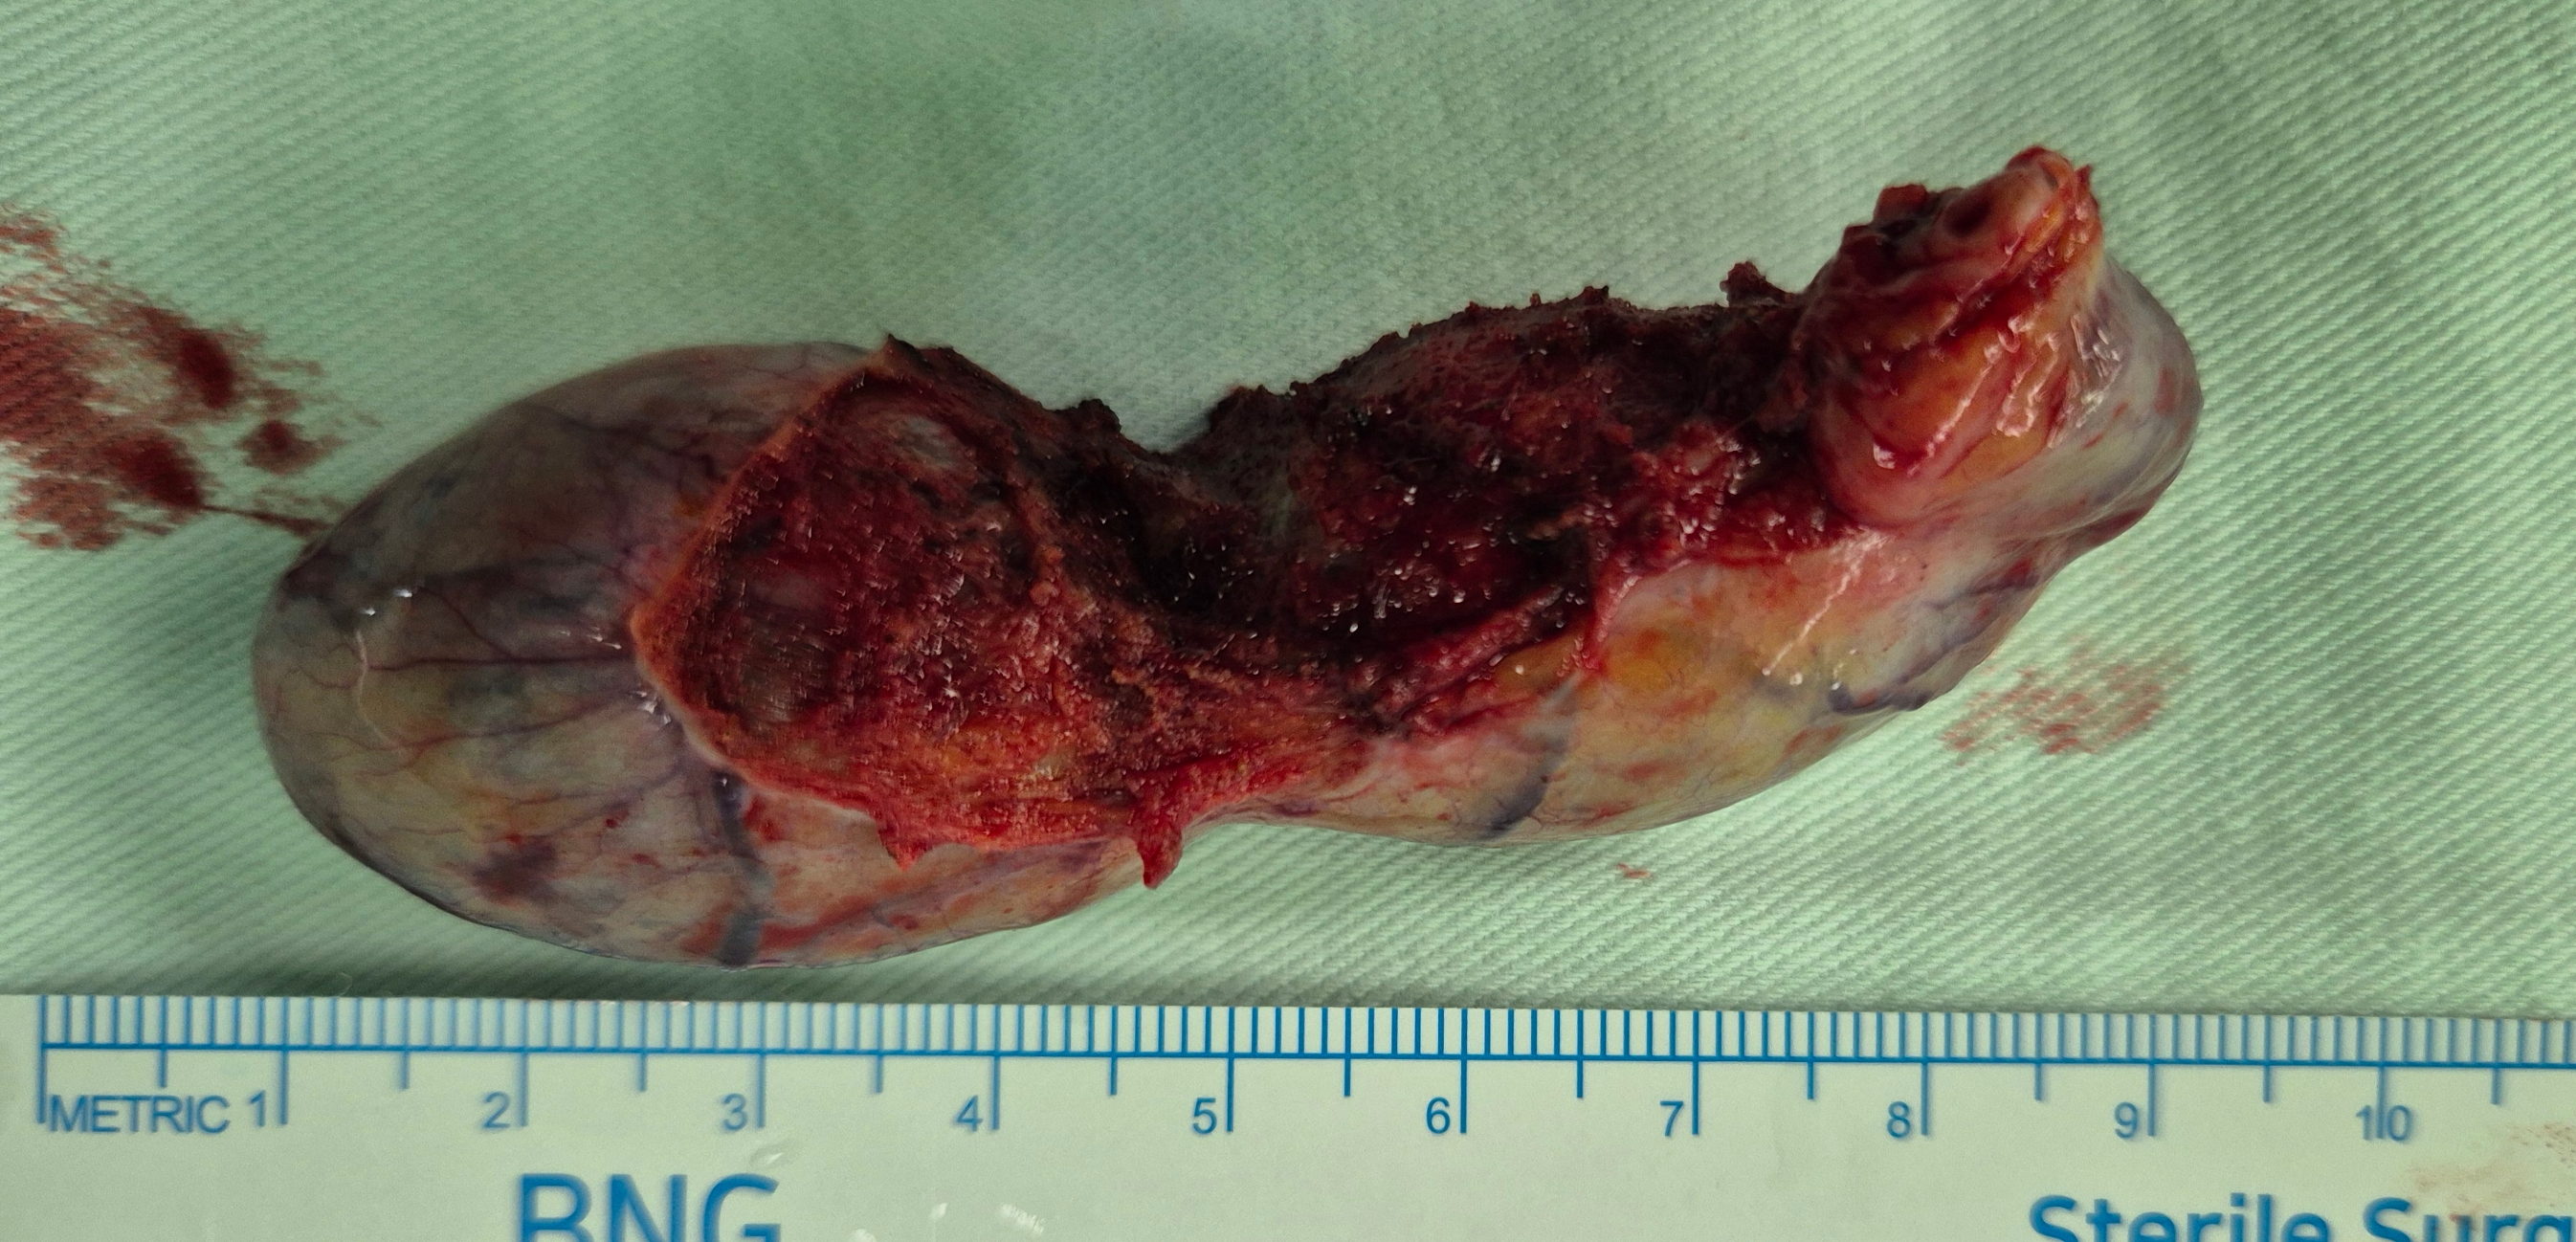

검진으로 진료보신 분으로 담낭용종 확인되었습니다. 우측 난소낭종도 있어 산부인과에서 동시에 수술진행했습니다.

방금 단일공 복강경 담낭절제술을 시행했습니다.

수술은 10분 걸렸습니다.